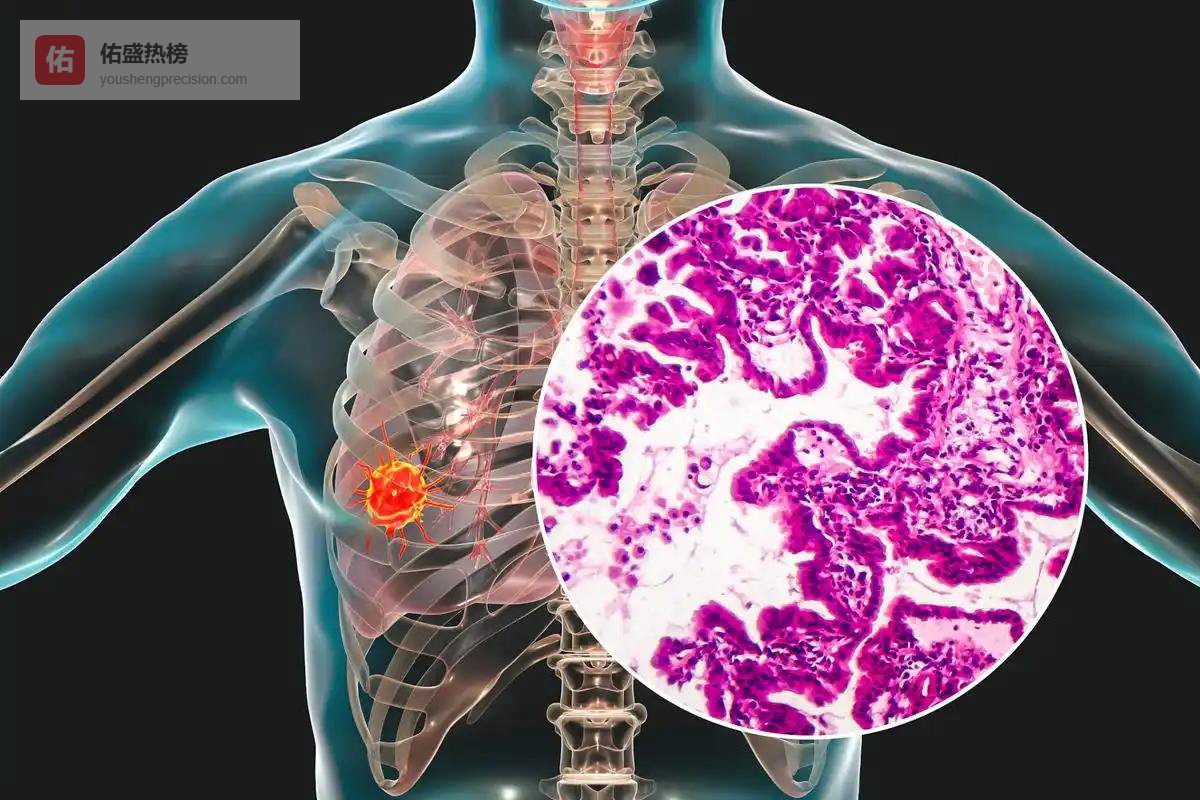

某些实体瘤(如肺癌、胃癌)会分泌促炎因子,刺激骨髓释放更多中性粒细胞,形成一种“类感染”状态。